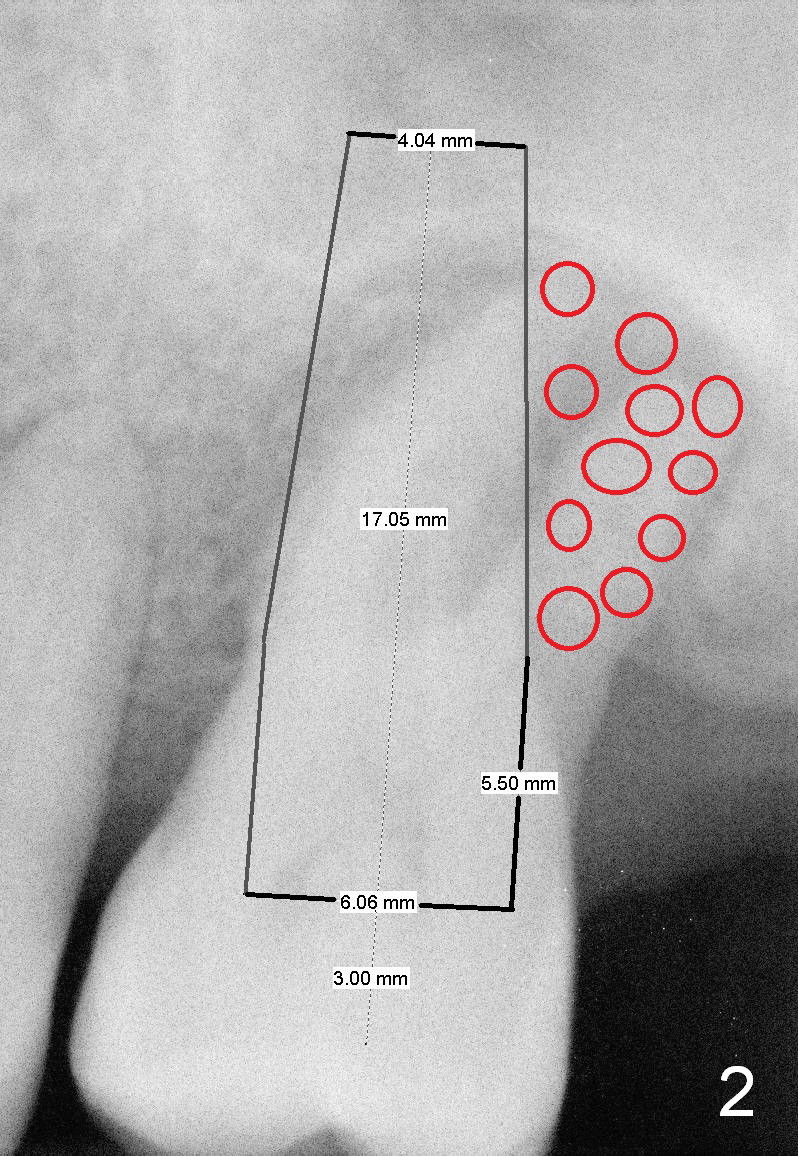

A 52-year-old man (DM) will return for #14 extraction and immediate implant nearly 2 years after #12 crown cementation. There is more bone loss distally than mesially. Clinically, the palatal recession is excessive (Fig.3). After socket debridement and 2% Xylocaine/1:50,000 Epinephrine gauze packing, osteotomy will be initiated in the buccomesial aspect of the septum, if the latter is present. Use 4.5 or 5x17 mm tap to test stability and more importantly determine how much thread exposure can occur palatally before placing a 14 or 17 mm long implant (Fig.2). A fair amount of bone graft will be inserted distopalatally (red circles in Fig.2). If primary stability is achieved, use an immediate provisional to close the socket opening.